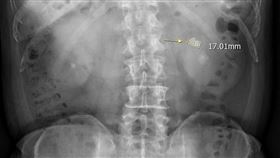

男狂喝1飲料!膀胱塞35顆石頭 恐怖成分曝

不少人喜歡喝碳酸飲料,但小心飲用過量可能危害健康。泌...

膀胱卡12顆巨石 醫切開赫見大魔王

人一生中會有10%的機率發生結石,尿路結石有多痛,過...